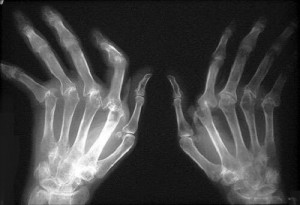

Основният и най-видим симптом е подуване или възпаление на ставите, което е свързано със силна болка. Най-засегнатите от ревматоиден артрит части на тялото са китките, лактите, раменете, краката, ръцете, бедрата, глезените и коленете. Почти винаги пациенти, които страдат от това заболяване имат усещане за скованост, особено когато се събудят сутрин.

Понякога се появяват и ревматоидни възли. Това са издатини по кожата (особено на задната част на ръцете и краката) или в тялото. Възпалението се превръща в деформацията на ставите, когато болестта влезе в напреднал стадий.